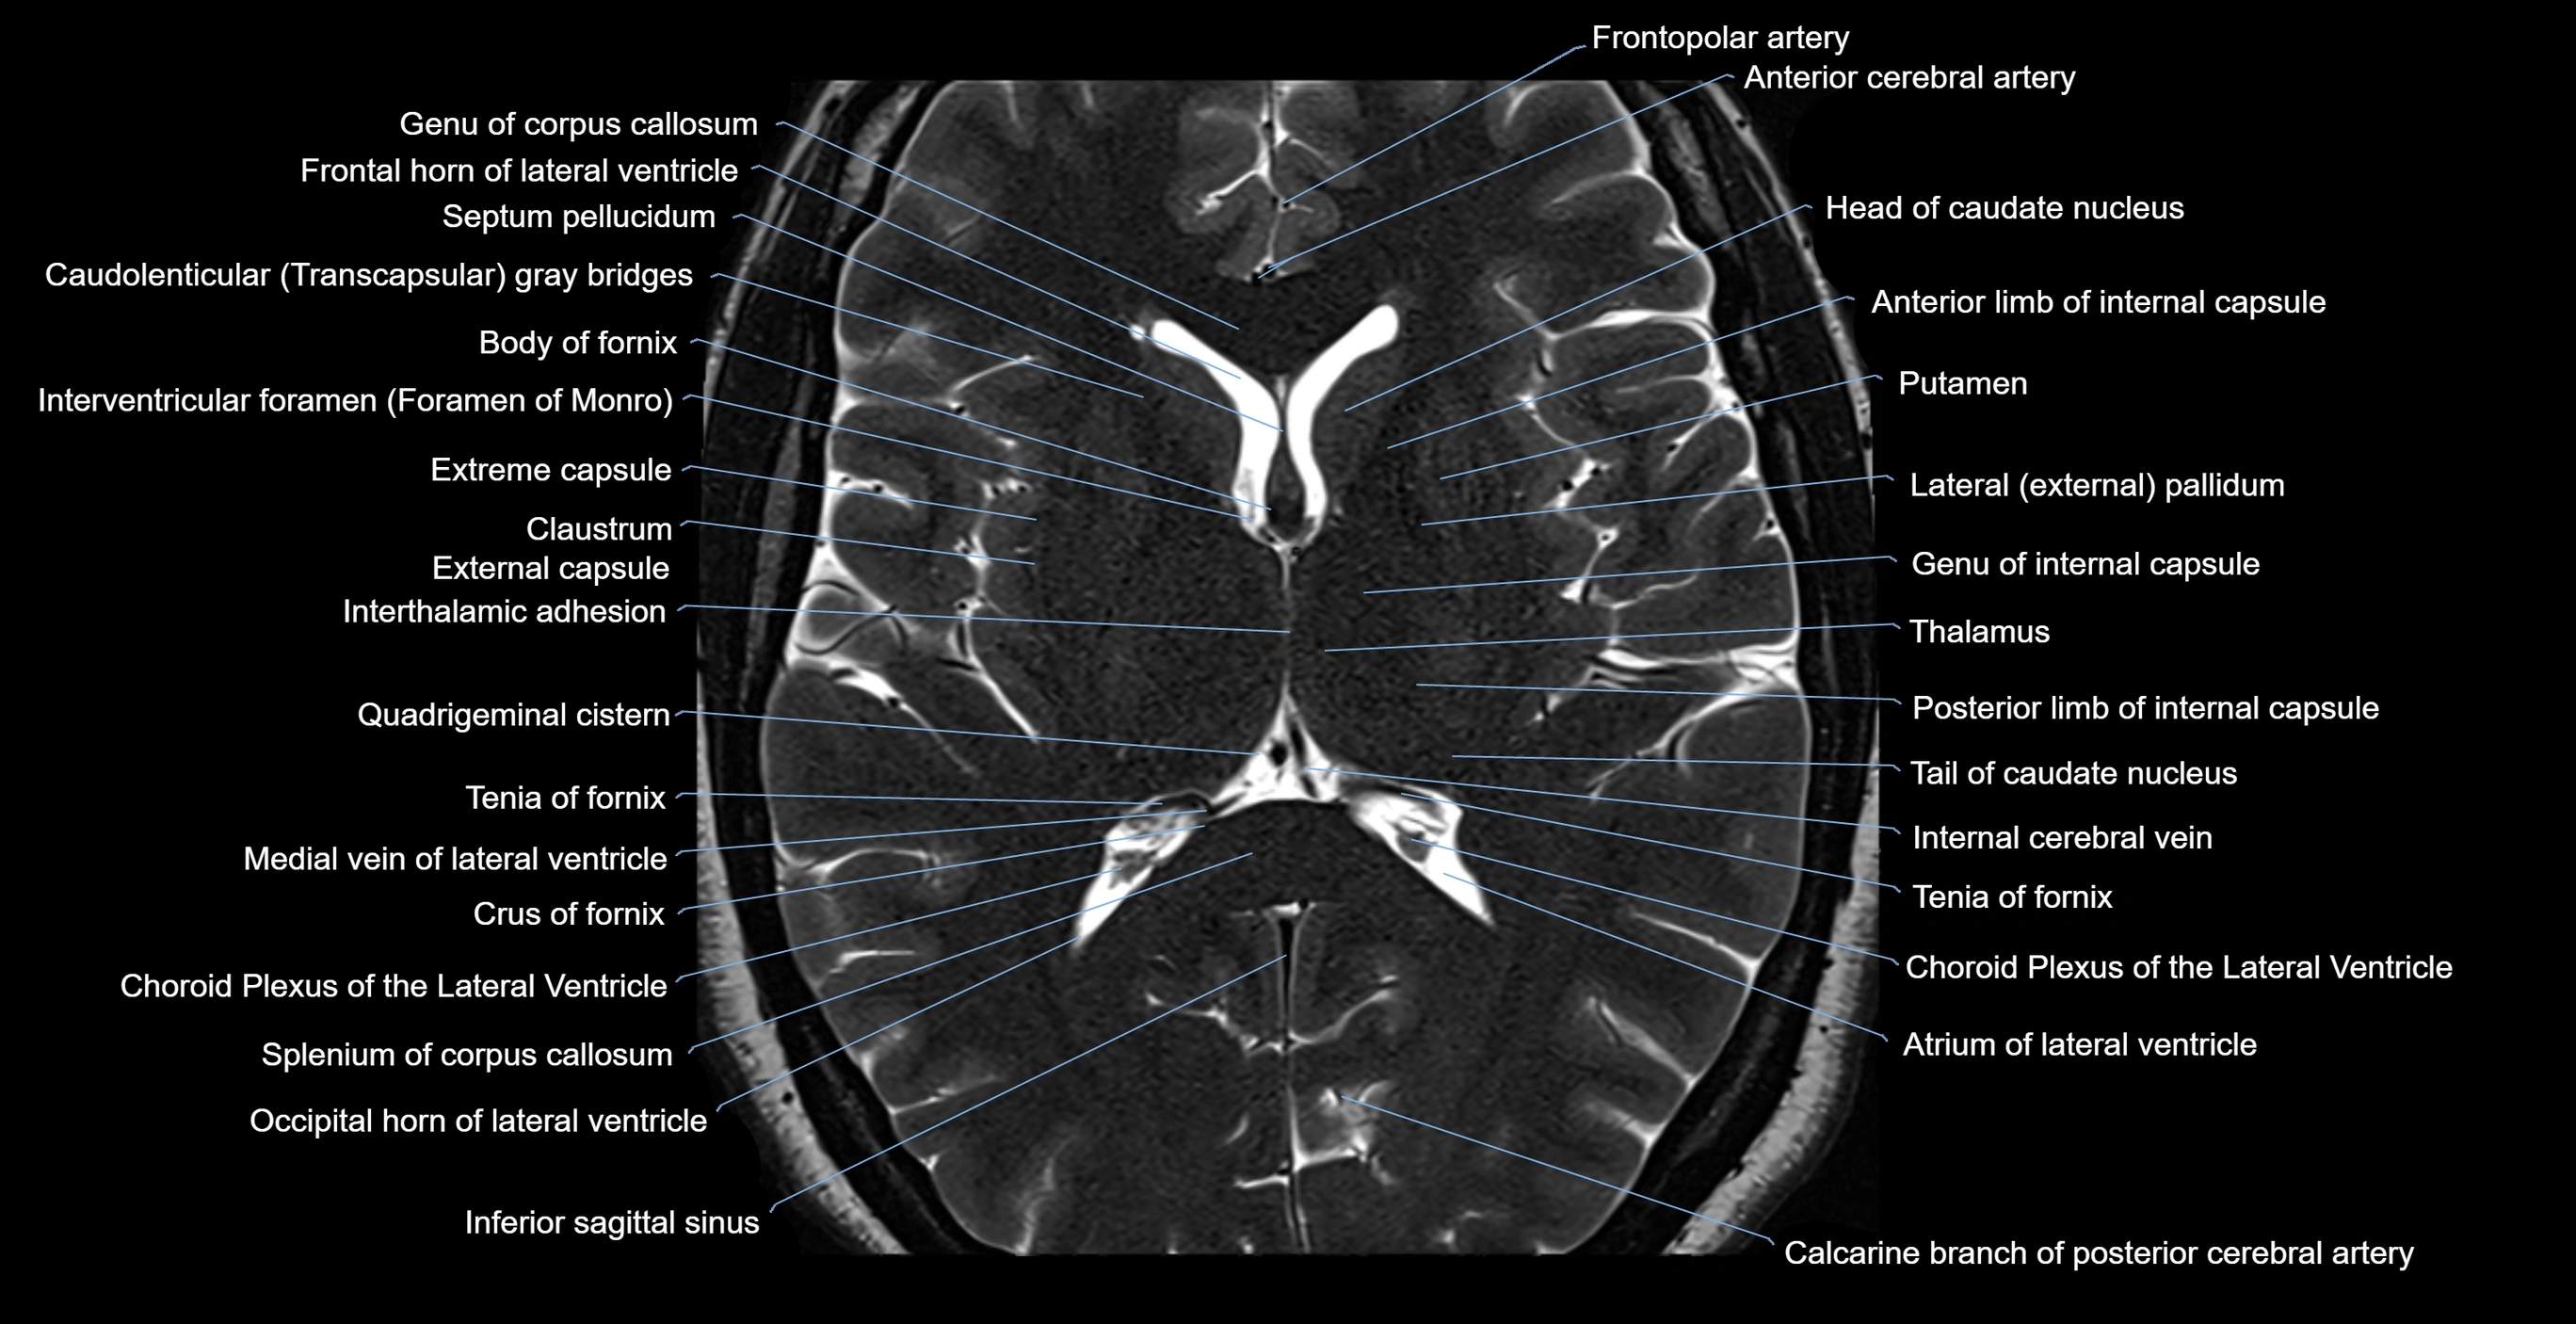

- Anterior limb of internal capsule

- Atrium of lateral ventricle

- Body of caudate nucleus

- Body of corpus callosum

- Body of fornix

- Body of lateral ventricle

- Calcarine branch of posterior cerebral artery

- Choroid plexus of the lateral ventricle

- Cistern of transverse fissure

- Column of fornix

- Corona radiata

- External capsule

- Extreme capsule

- Frontal horn of lateral ventricle

- Frontopolar artery

- Genu of corpus callosum

- Head of caudate nucleus

- Inferior sagittal sinus

- Internal cerebral vein

- Interthalamic adhesion

- Interventricular foramen

- Occipital horn of lateral ventricle

- Posterior limb of internal capsule

- Putamen

- Septum pellucidum

- Splenium of corpus callosum

- Straight sinus

- Superior thalamostriate vein

- Tail of caudate nucleus

- Tenia of fornix

- Thalamus